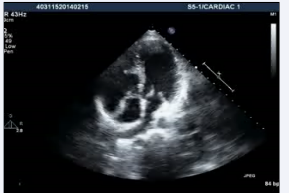

. Additionally, the patient had a subaortic conus and aortomitral discontinuity with a possible ventricular septal defect (Figure 3, video3)

Figure 3: Transthoracic echocardiogram high parasternal view showing presence of subaortic conus with aortomitral discontinuity.